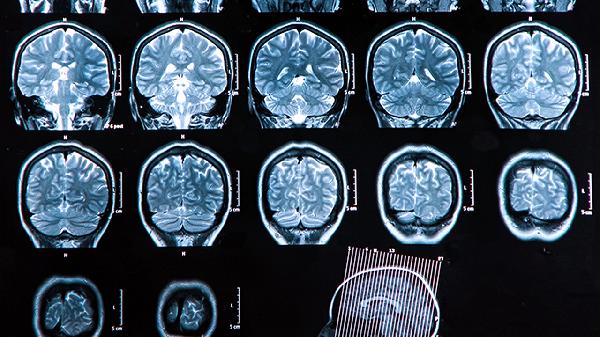

脑血栓片是一种中成药,主要成分包括丹参、川芎、红花等活血化瘀类中药。该药物通过改善脑部血液循环、抑制血小板聚集等机制,对缺血性中风恢复期的肢体功能障碍有一定改善作用。临床常用于中风后遗症如半身不遂、言语不利等症状的辅助治疗,可配合康复训练使用。